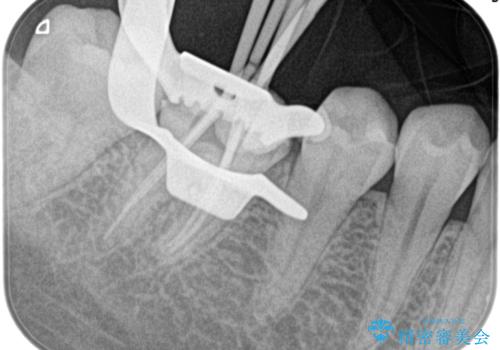

- 奥歯がズキズキ痛いことを主訴に来院されました。

検査の結果、診断を症候性不可逆性歯髄炎、症候性根尖性歯周炎とし抜髄を行っております

根管充填はhydraulic condensation techniqueにて行なっております。

シーラーはWell pulp ST 使用